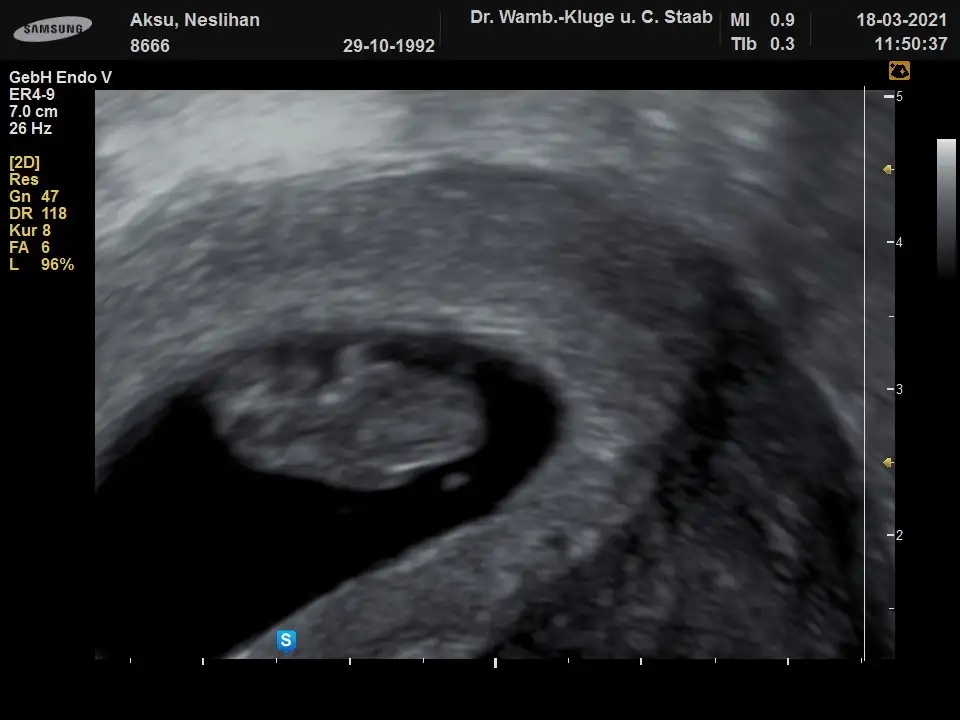

Kız gibi görünüyor canımEki Görüntüle 2824646 banada bakarmisiniz

Canim banada bakabilirmisnn 9.hafta vajinal ultrasyonOzmaan erkek görünüyor